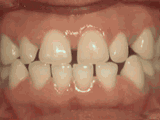

Espacios entre los dientes

A este paciente le molestaban los espacios entre sus dientes. El uso de frenos cerró estos espacios y le proporcionó una mordida ideal en 24 meses. Lleva puesto un retenedor fijo para mantener los espacios cerrados.